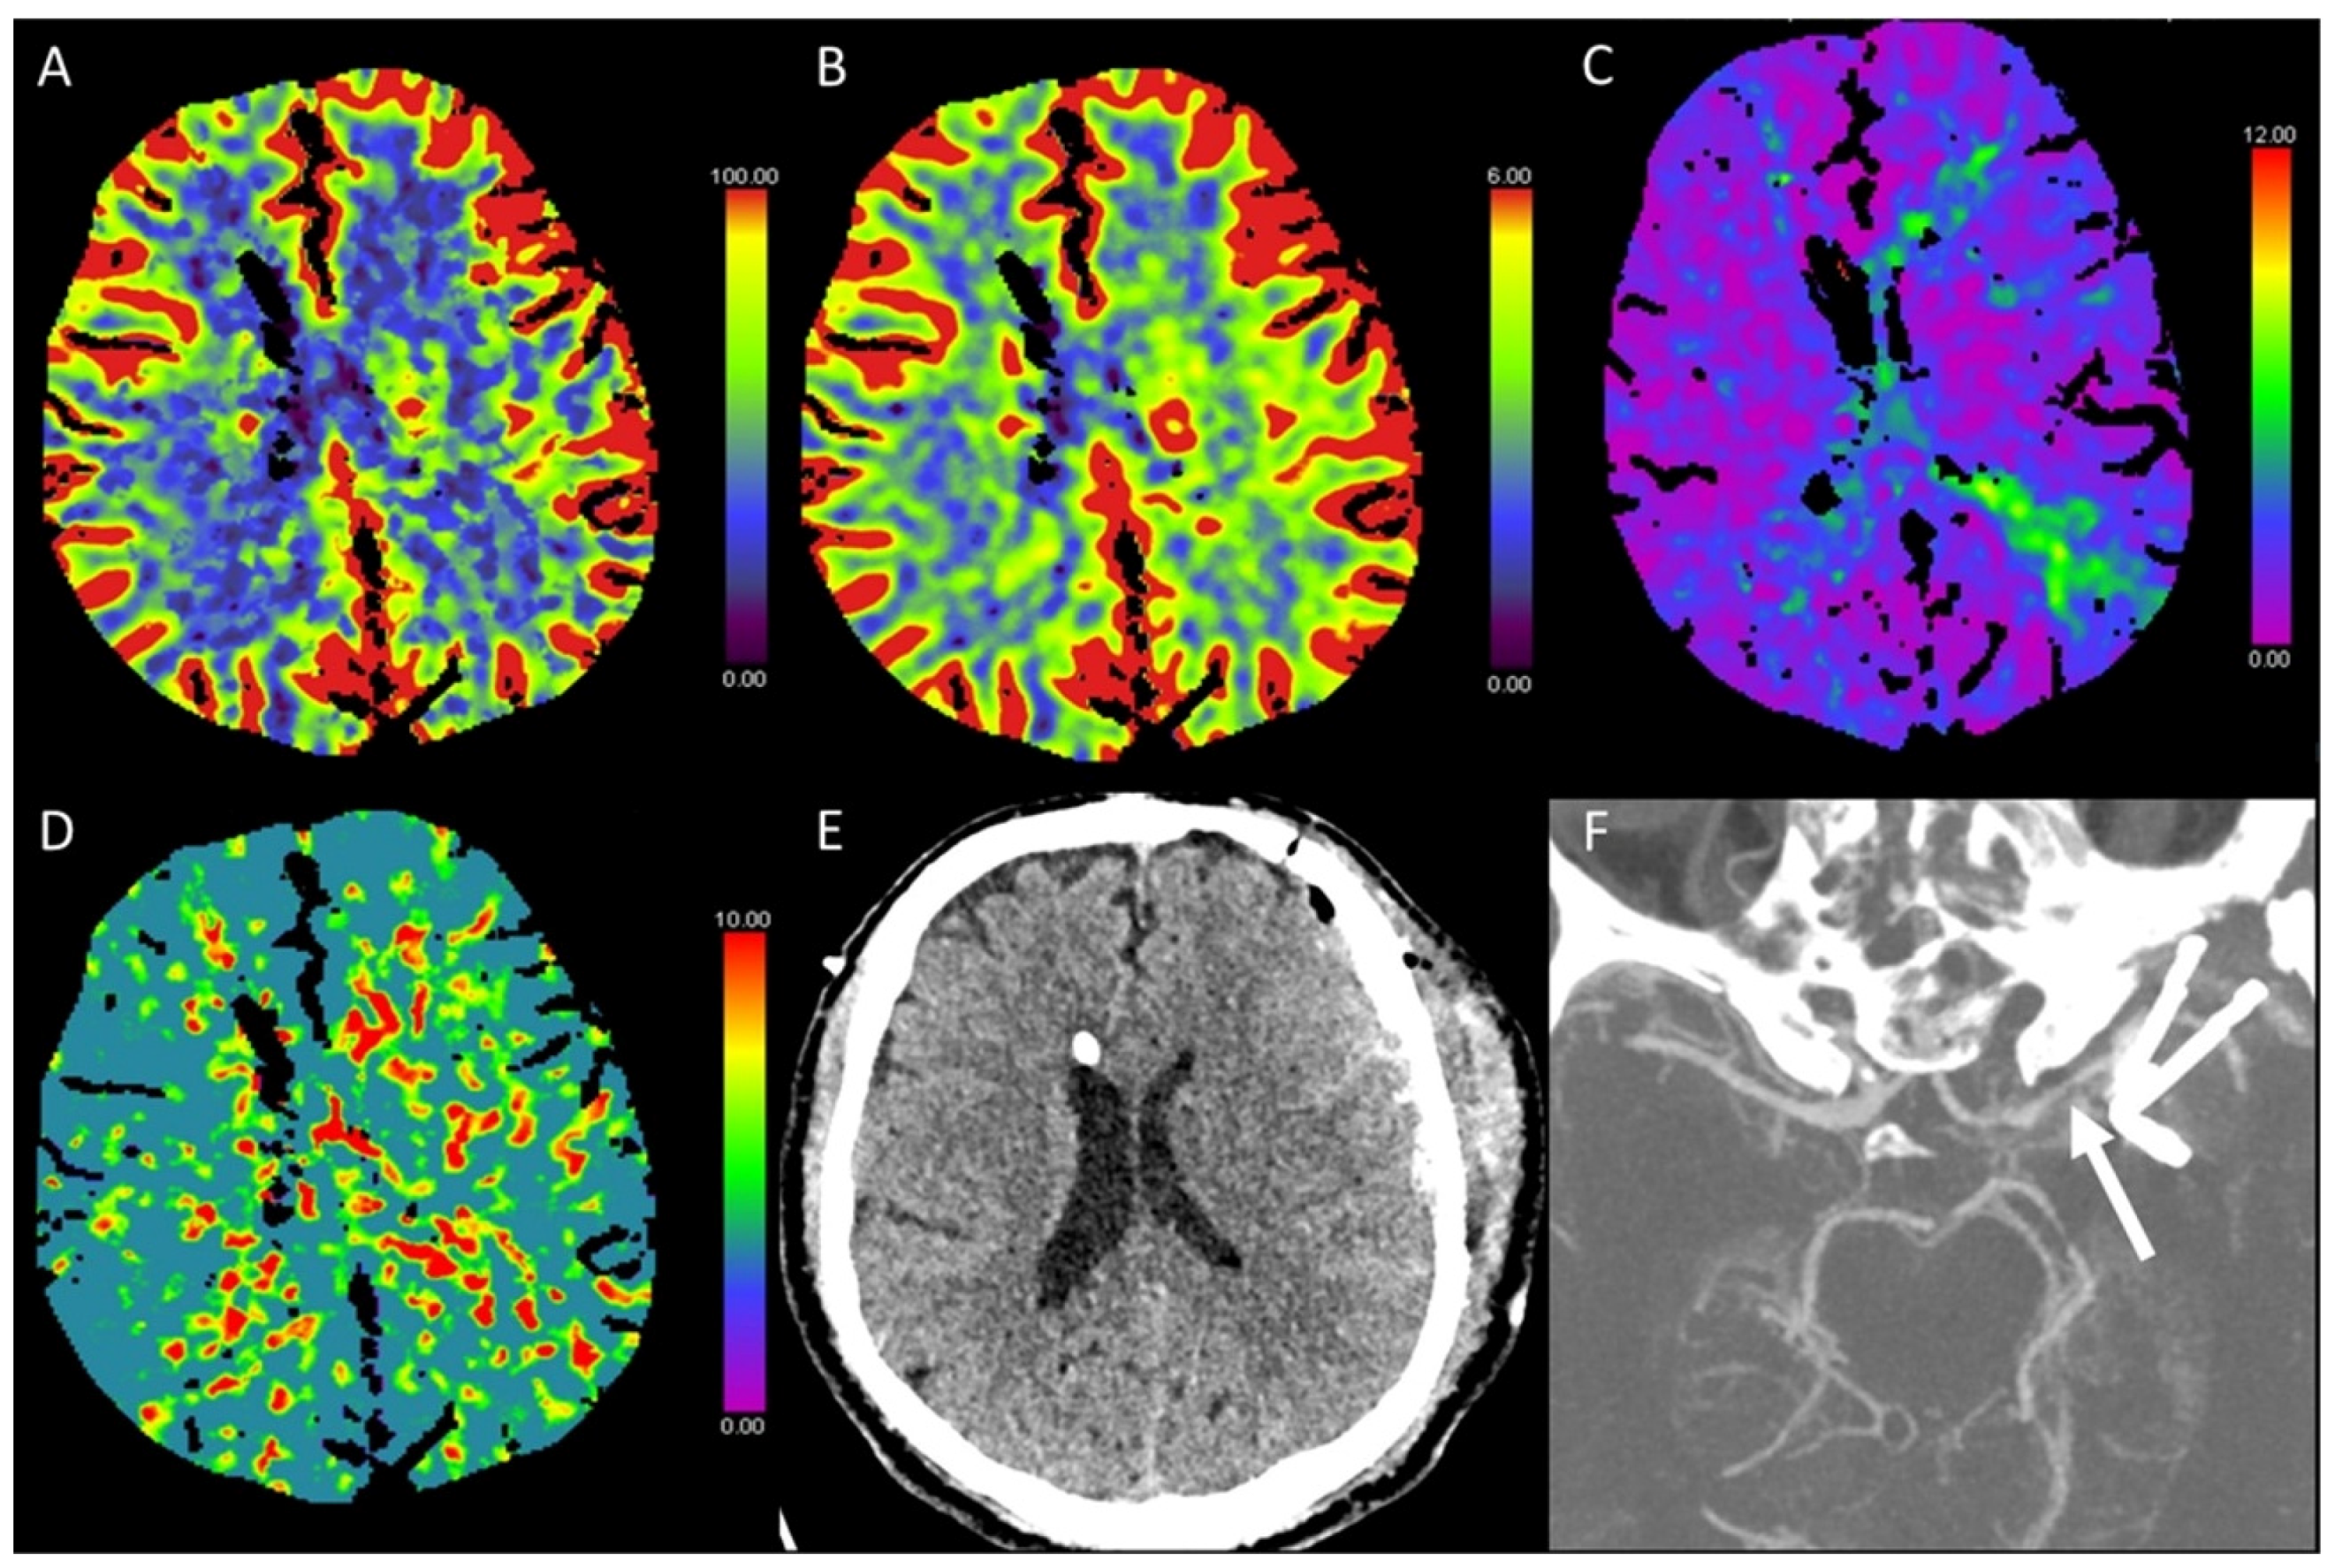

3.1. Acute Supratentorial Stroke

3.5. Hypotensive Cerebral Infarction (HCI) with Watershed Infarcts/Border Zones

3.6. Vasospasm